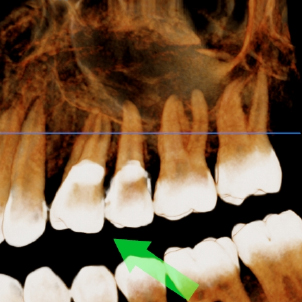

La RDD es muy exacta y fácil de interpretar como las placas convencionales de Rayos X; pero además puede ser aumentada 300 veces su tamaño, puede modificarse el contraste y ajustarse el tono del color y así detectar los problemas escondidos a las placas convencionales.